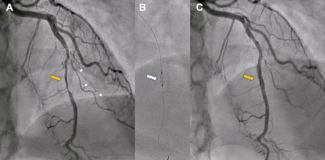

A 69-year-old diabetic man with morbid obesity underwent elective angioplasty for a chronic total occlusion of the left anterior descending coronary artery via right radial and right femoral access.